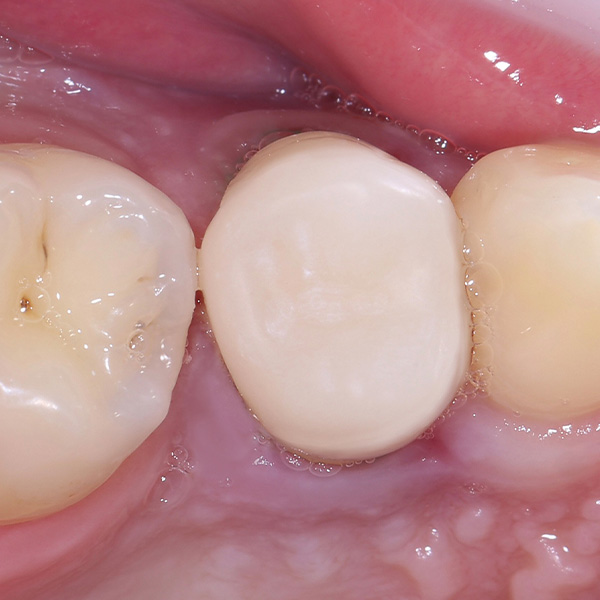

VITA ENAMIC multiColor Endokrone: Ausgangssituation vs. Finales Ergebnis

Ergebnis: VITA ENAMIC multiColor integrierte sich harmonisch in die natürliche Zahnsubstanz. Die insuffiziente Kompositfüllung an Zahn 14 (od) hatte zu Entzündungen im Zahnzwischenraum geführt.